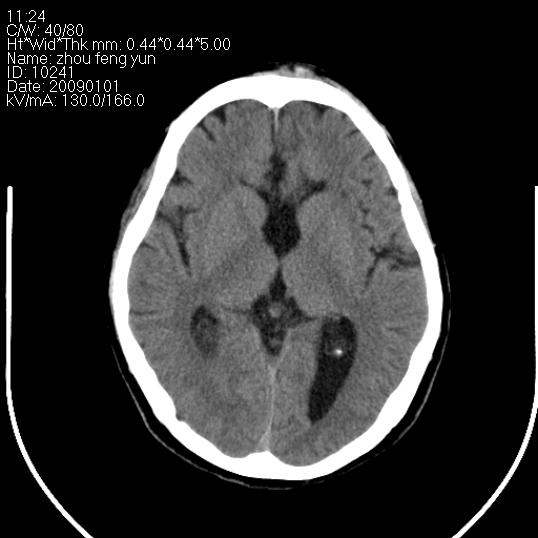

以下是引用hhcckk在2009-1-1 16:39:00的发言:[br]胼胝体嘴、膝部及部分体部发育不全,为囊状影替代,两侧侧脑室分离,脑室后角扩张[br][br]诊断:胼胝体发育不良[br][br]胼胝体发育不良(dysgenesis of the corpus callosum)是最常见的颅脑畸形,是胚胎期背部中线结构发育不良的一种形式。主要包括胼胝体缺如和部分缺如。胼胝体发育不良还可合并其他畸形,如胼胝体脂肪瘤、蛛网膜囊肿、脑膨出、chiari畸形、灰质异位症、脑回畸形等。[br][br]ct诊断要点:[br]1. ct横断扫描可见两侧侧脑室明显分离,脑室后角扩张,形成典型的蝙蝠翼状侧脑室外形。[br]2. 第三脑室扩大并向上插入两侧脑室体部之间,严重者第三脑室可上移到两侧大脑半球纵裂的顶部。在ct冠状扫描位显示更清。[br]4. 胼胝体畸形常伴有脂肪瘤,可测到其特征性脂肪密度。部分脂肪瘤的边缘可出现线样钙化[br]